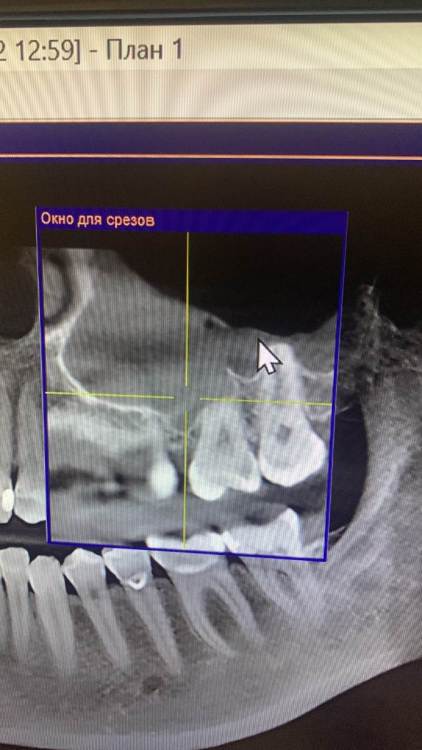

KOCTb Опубликовано 1 января, 2024 Поделиться Опубликовано 1 января, 2024 Здравствуйте коллеги. Может кто-то подскажет полезного. Пациентка. Лет 6 назад пришла с симптоматикой пульпита во втором секторе. На некоторых зубах были пломбы, без криминала. Зубы были проверены на витальность. Все живые. Пальпаторно передняя стенка ВП давала лёгкую чувствительность. Сделали КТ. Апикальных изменений не выявлено, а в пазухе слева признаки гайморита. Заполнена была бальше чем наполовину. Отправил к ЛОРу. Пролечили. Анатомическое строение не очень понравилось. С тех пор каждую зиму у неё обострение ВЧ синусита слева. Иногда даже два раза бывает. Каждый раз ЛОР в направляет к стоматологу и говорит, что гайморит одонтогенгый. Врачи рентгенологи в описании иногда там находят одонтогенгую кисту… Года два назад пациентка сходила поменяла все пломбы, на всякий пожарный. Со слов зубы все были витальные при лечении. Ну и собсвенно опять ВЧ синусит. Смущает анатомическое строение между 25 и 26 зубом. Не может ли там через периодонтальную щель «сифонить» ? Говорит между зубами иногда какой-то дополнительный дискомфорт есть. Ссылка на комментарий

KOCTb Опубликовано 15 января, 2024 Автор Поделиться Опубликовано 15 января, 2024 19 часов назад, Astronaft сказал: Здравствуйте. 6 лет назад: подробнее про симптомы пульпита? как полечили гайморит и чего добились? Анатомия действительно интересная. Интуитивно, или естественная впадина которая способствует застою либо проблемы в соустье вызывают застой и кислотный секрет лизирует самое слабое место. Опять же интуитивно, пациентке приказать зубы не трогать, не ходить выискивать проблемы. Очень подробно расспросить анамнез, в том числе что помогает, что запускает синусит. Если соустье открыто то я бы рекомендовал регулярно промывать физраствором с ЭДТА и выждать. Здравствуйте. Ну как обычно пульпитная симптоматика при ВЧ синусите. Разлитые периодические боли в верхнем секторе, с непонятной локализацией. Пальпаторно передняя стенка ВЧ пазухи давала болезненность. От 25 до 27 зуба. На КТ зубов затенение в ВЧ пазухе. Отправил тогда к ЛОРу. Подробности лечения у ЛОР врача тогда не знаю. Синуситы в холодное время года. Соустье пародонтальным зондом не выявлено. Носо-ротовая проба также отрицательная. Но тут и понятно если и есть ход, то крайне мизерный. Там слизистой завалено всё. Ссылка на комментарий